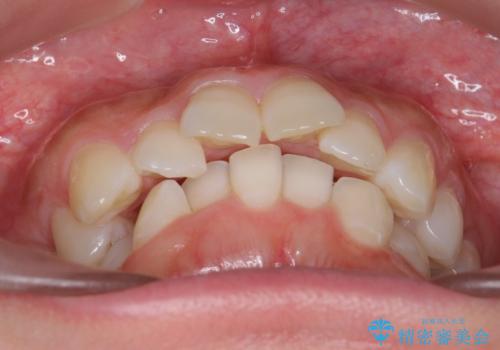

前歯をさげたい 歯を抜かずに マウスピース矯正で治したい

- 上の前歯が出ているとのことで来院。

歯を抜かずに、上の奥歯を後ろにさげつつ上の前歯を小さく少し削る処置を行い前歯の角度を修正しました。

右上下の奥歯もすれ違い咬合も、治療で改善しています。

下の前歯が生まれつき3本でしたので上下の正中は合わない仕上がりとなります。